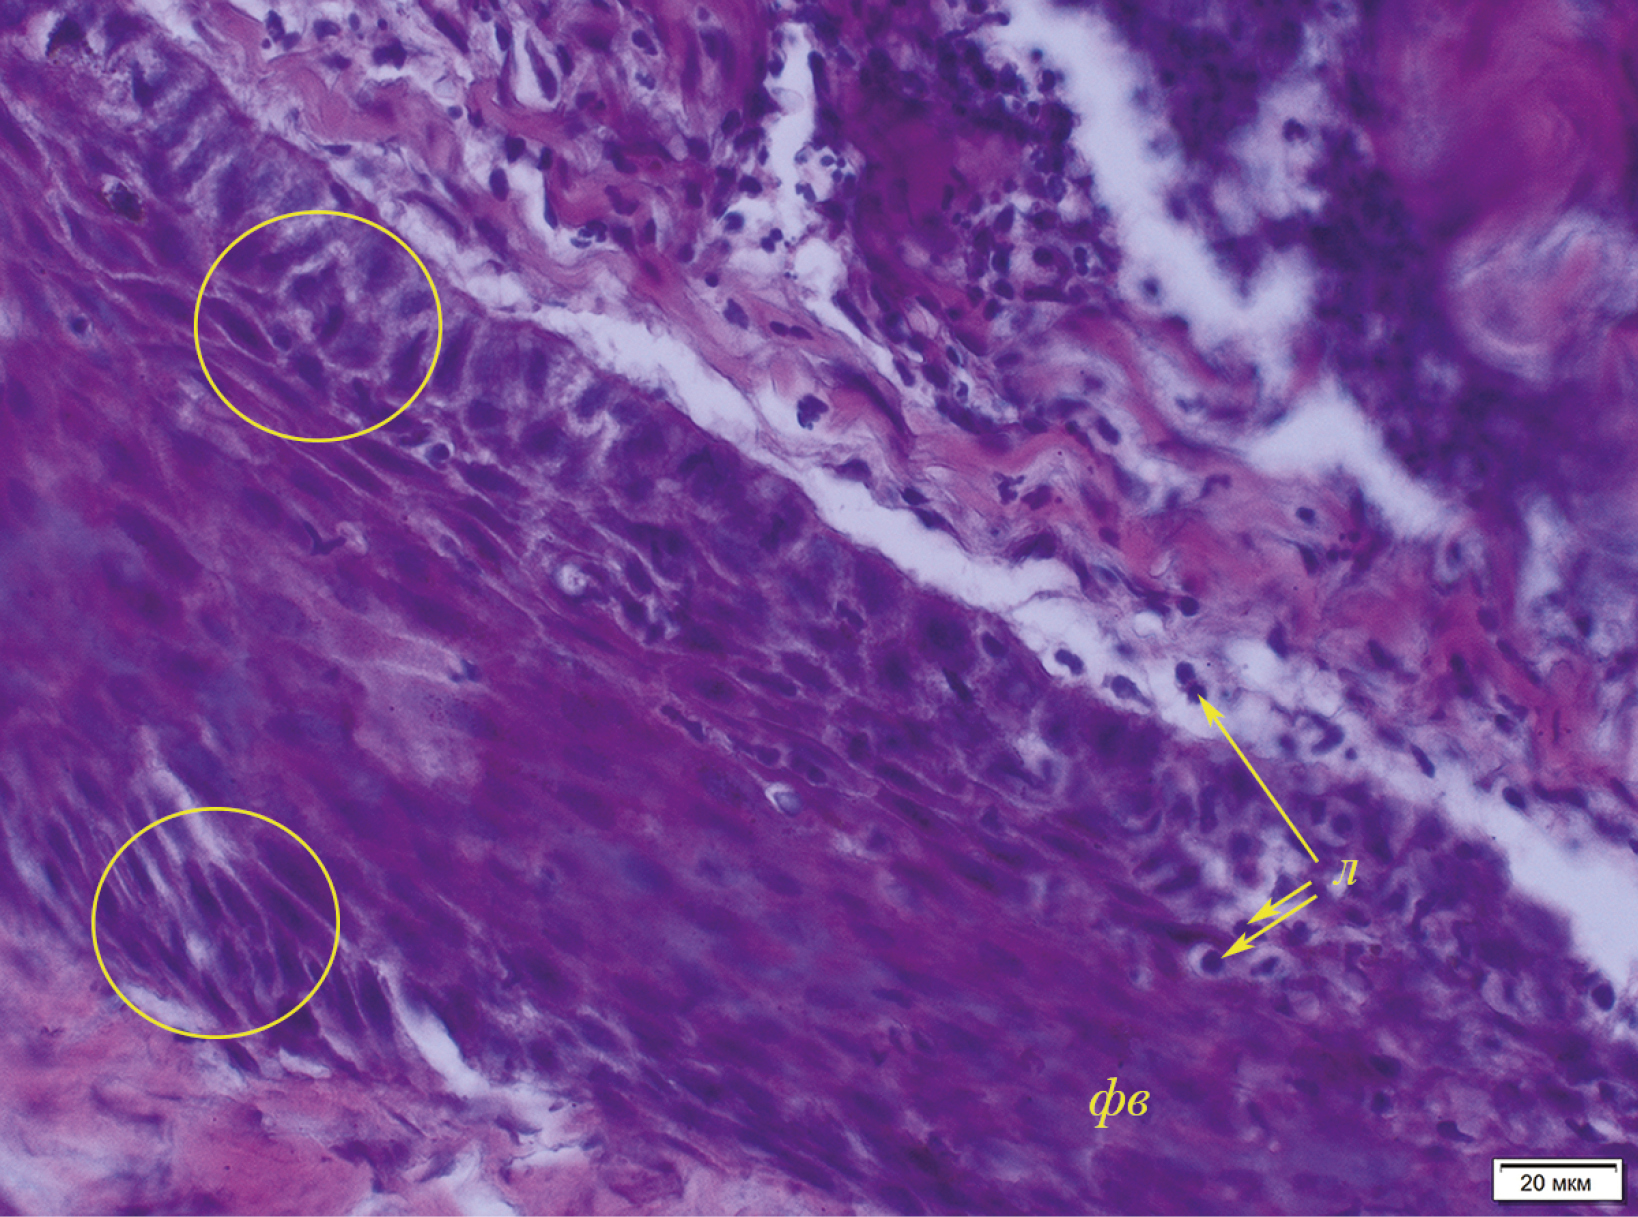

Одновременно с процессом койлоцитоза в субэпидермальных слоях кожи имеются очаги воспаления, локализующиеся в основном периваскулярно и частично перифолликулярно (рис. 11). В более глубоких слоях воспаление усиливается, локализуясь, в том числе, и вокруг потовых желез. Воспалительный инфильтрат представлен лимфоцитами с небольшим количеством гистиоцитов. В срезах кожи с поражениями также обнаружен экзоцитоз, связанный с тем, что лимфоциты мигрируют в волосяные фолликулы (рис. 12). Клетки влагалища волосяного фолликула отечны, присутствуют явления спонгиоза. Описанный комплекс патологических изменений кожи встречался наиболее часто при исследовании пораженных участков у байкальской нерпы.

Рис. 12. Миграция лимфоцитов в волосяной фолликул (экзоцитоз) и спонгиоз эпителиоцитов эпителия волосяного влагалища (№ 1, самка, 2+): фв – волосяной фолликул, л – лимфоциты, мигрирующие в фолликул (указаны стрелками). В выделенных желтым цветом областях показаны эпителиоциты с признаками спонгиоза (отечные эпителиоциты, отделенные друг от друга). Окраска гематоксилином с эозином.

Процесс миграции лимфоцитов в эпителий волосяного фолликула у байкальской нерпы остается неясным, поскольку роль внутриэпидермальных лимфоцитов недостаточно изучена. В литературе обсуждались несколько возможных функций таких лимфоцитов: участие в элиминации клеток, зараженных вирусом или злокачественно перерожденных; стимуляция регенерации эпителия и регуляция состояния межклеточных контактов (Мяделец, 2000). Наличие спонгиоза в клетках волосяных фолликулов в коже байкальской нерпы при экзоцитозе лимфоцитов подтверждает последнюю версию. Тем не менее остается неясным, почему описанные патологические явления отмечены только в волосяных фолликулах и какие патогены могли запустить данный процесс?